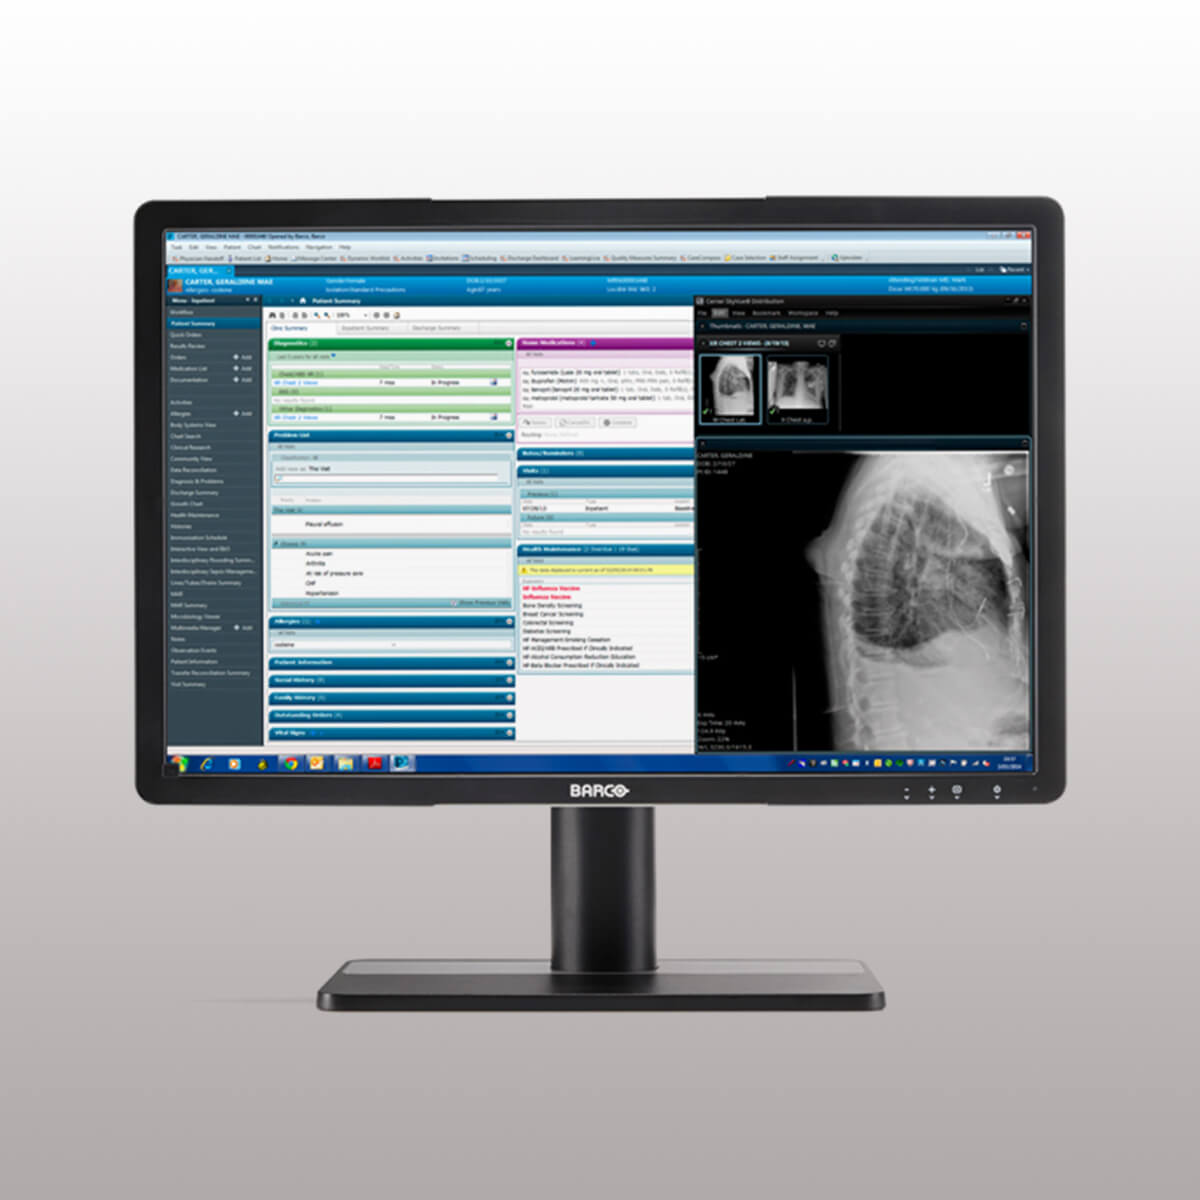

تکنولوژی Color Display

تکنولوژی Color Display امکان مشاهده تصاویر به صورت رنگی و با کیفیت بالا را فراهم میکند.

استاندارد DICOM

تصویربرداری دیجیتال و ارتباطات در پزشکی (Digital Imaging and Communications in Medicine – DICOM) یک استاندارد بینالمللی بوده که به منظور بهبود ارتباط تصاویر دیجیتال در رادیولوژی تنظیم شده است. یکی از کاربردهای استاندارد DICOM، تعریف یک تابع جهت تنظیم مقیاس خاکستری صفحه نمایشهای مورد استفاده در تصویربرداری پزشکی است. همچنین امکان ارتباط بین ایستگاههای کاری PACS، سیتی اسکنرها، تصویربردارهای MR، دیجیتالسازهای فیلم، آرشیوهای مشترک، پرینترهای لیزری، کامپیوترها و پردازندههای مرکزی مختلف را در بخش رادیولوژی فراهم میکند.

مزایای استاندارد DICOM عبارتند از:

– کیفیت تصویر ثابت

– مقرون به صرفه

تکنولوژی IPS WideView

تکنولوژی IPS WideView یک معماری LCD پیشرفته است که حتی در صورت وجود زاویه دید گسترده، تصاویر را با رنگ سیاه یکنواختتر و کنتراست بهتر، نمایش میدهد. به طور خلاصه، با استفاده از این تکنولوژی امکان افزایش کیفیت تصویر، مشاهده جزئیات بسیار ظریف در نواحی تاریک تصویر و عملکرد سریع و کارآمد هنگام کار کردن با سیستمهای چند کاربره، وجود دارد.

مزایای تکنولوژی IPS WideView عبارتند از:

– یکنواختی در رنگ سیاه و کنتراست عالی حتی در صورت وجود زاویه دید گسترده

– دقت و کارایی بالا هنگام کار کردن با سیستمهای چند کاربره

تکنولوژی Consistency Sensor

به دلیل استفاده از یک سنسور تثبیت کننده تصویر (Consistency Sensor) در قسمت جلوی نمایشگر، با روشن شدن صفحه نمایش، کیفیت تصویر به طور اتوماتیک بهینه میشود.

سیستم پزشکی QAWeb

سیستم پزشکی QAWeb یک سرویس آنلاین بوده که به کاربران کمک میکند تا از تضمین کیفیت با درجه بالا اطمینان حاصل کنند. این سیستم به عنوان یک ابزار مبتنی بر وب میتواند برای کالیبراسیون، تضمین کیفیت و مدیریت سرمایه، به آسانی استفاده شود.

مزایای سیستم پزشکی QAWeb عبارتند از:

– افزایش زمان فعالیت ایستگاههای کاری

– تضمین کیفیت و ثبات تصاویر در هر لحظه

– عدم وقفه در روند مشاهده تصاویر